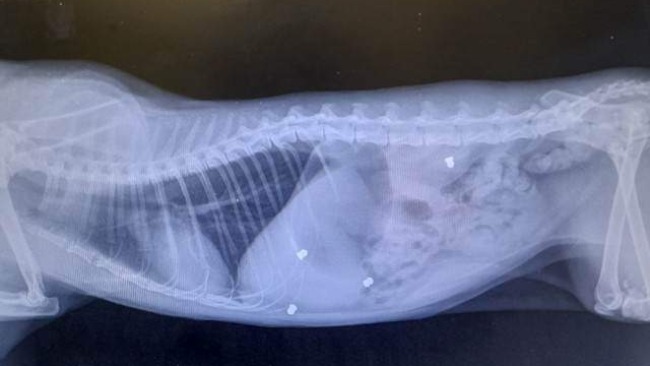

Od kilku lat dokarmiam i kastruje koty wolnożyjące na działkach,koty są piękne, zadbane i coraz bardziej zaczynają mi ufać,ale zdarzały się przypadki,że koty znikają w tajemniczych okolicznościach i już nigdy nie wracają albo wracają po jakimś czasie kulejąc i boją się mnie od nowa. Od jakiegoś czasu wiem,że ktoś strzela do nich z wiatrówki. Jeden kocurek zabrany z działek poszedł do adopcji i okazało się,że ma w ciele kilka śrutów.